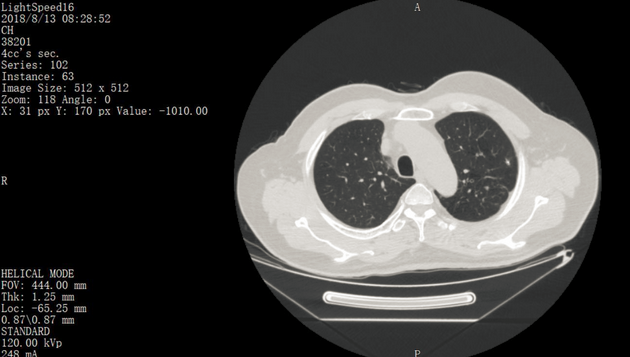

ct打印胶片怎么用远程就医、转院就医时,CT核磁DICOM电子胶片的重要性!【就医知识】_https://www.jmylbn.com_新闻资讯_第3张

(胶片模式)